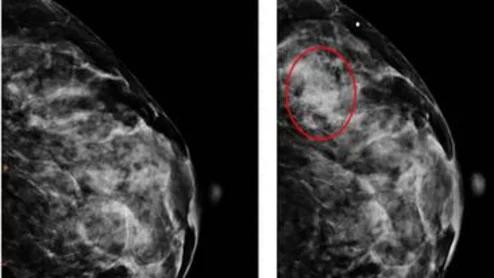

breast cancer mammography screening mammogram scheduling

Thanks to AI, clinicians can use mammograms to do a lot more than identify signs of breast cancer. Researchers explored data from nearly 50,000 patients, presenting their findings in Heart.